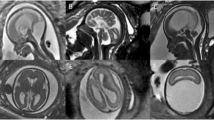

In case 3, US showed microcephaly, hypoplastic corpus callosum and diffuse parenchymal calcifications. MRI at 25 weeks of gestation (Fig. 4) confirmed these findings and also showed ventriculomegaly with diffuse polymicrogyria and opercular dysplasia.

Case 3. Brain MRI at 25 weeks of gestation. a–d T2-weighted sagittal (a) and coronal (b, c), and T1-weighted coronal (d) slices are shown. The morphology of the posterior fossa structures is normal. The supratentorial space is small, with enlarged pericerebral space. The corpus callosum (arrowheads in a and b) is very thin. The ventricles are enlarged and the cortex is very thin and irregular, accounting for diffuse polymicrogyria. Note the bilateral opercular dysplasia and diffuse laminar necrosis with T2 hypointensity/T1 hyperintensity (dotted arrows) of the cortex